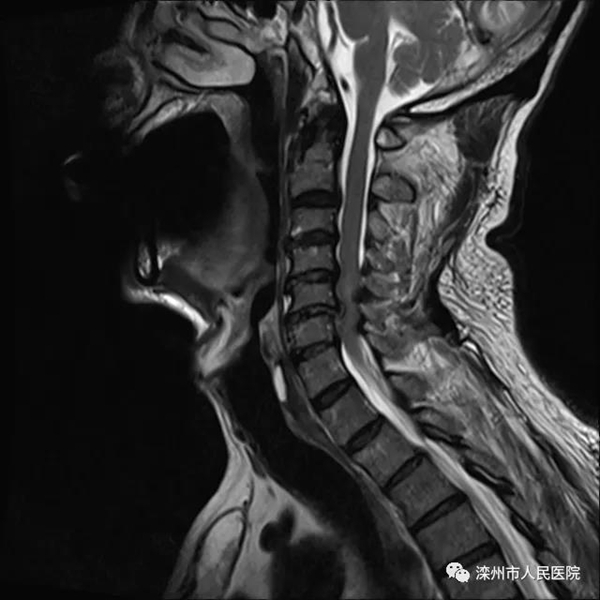

经颅骨牵引治疗,颈椎复位良好。但患者肢体活动障碍逐渐加重,并逐渐出现二便失禁,行核磁检查提示颈椎间盘突出、脊髓受压。

颈椎复位后核磁显示脊髓受压